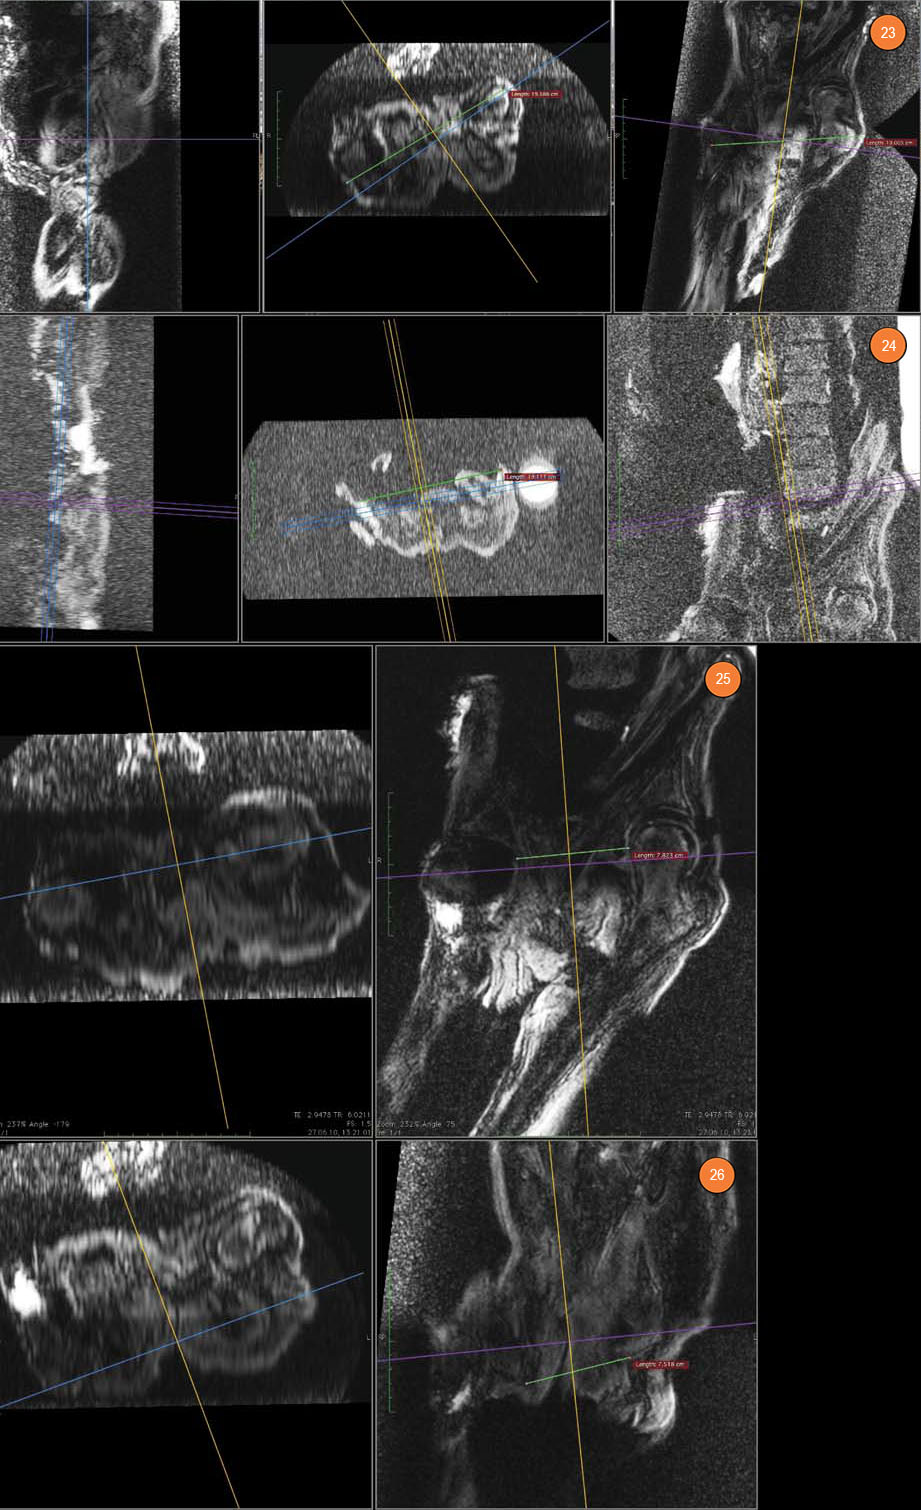

Что касается костей бедра, то в дистальной части диафизарной полости левой бедренной кости обнаружены отечно-склеротические овоидные очаги общим размером 19×16×76 мм. В метаэпифизарной зоне и в дистальной части диафизарной полости правой бедренной кости также обнаружены серийные отечные очаги общим размером 13×15×85 мм. Все эти изменения можно оценить как прижизненные остеомиелитические в остро-подострой фазе.

Рис. 27. Строение крестца. Рис. 28. Левое бедро. В дистальной части диафизирной полости — отечно-склеротические очаги. Рис. 29. Правое бедро. А и Б — параллельные срезы. В дистальной части диафизирной полости — отечно-склеротические очаги

В костях левой стопы выявлены очаги с отечной периферией и с МР-плотными темными центральными зонами. Эти изменения можно интерпретировать как проявления прижизненного инфекционного или, что более вероятно, метастатического процесса. Аналогичные, но менее интенсивные очаги выявлены в костях правой стопы.

Рис. 33. Правая голень — большеберцовая кость. Рис. 34. Правая голень — малоберцовая кость, дистально (А) и проксимально (Б)

Рис. 35. Левая стопа. А — очаг в кубовидной, таранной кости, в плюсневых костях. Б — очаги в кубовидной, пяточной кости и в латеральной лодыжке, в V плюсневой кости. В — очаги в кубовидной, пяточной кости, в I плюсневой кости, в проксимальной фаланге I пальца и в дистальном диафизе большеберцовой кости. Рис. 36. Правая стопа. А — очаги в I плюсневой кости и в проксимальной фаланге I пальца. Б — очаг в правой кубовидной кости